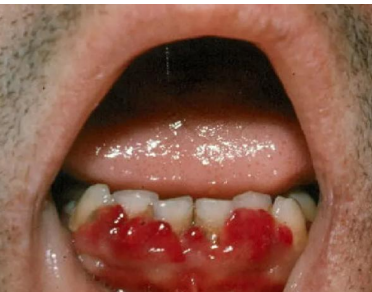

Scurvy (vitamin C deficiency)

Scrobutic gingivitis